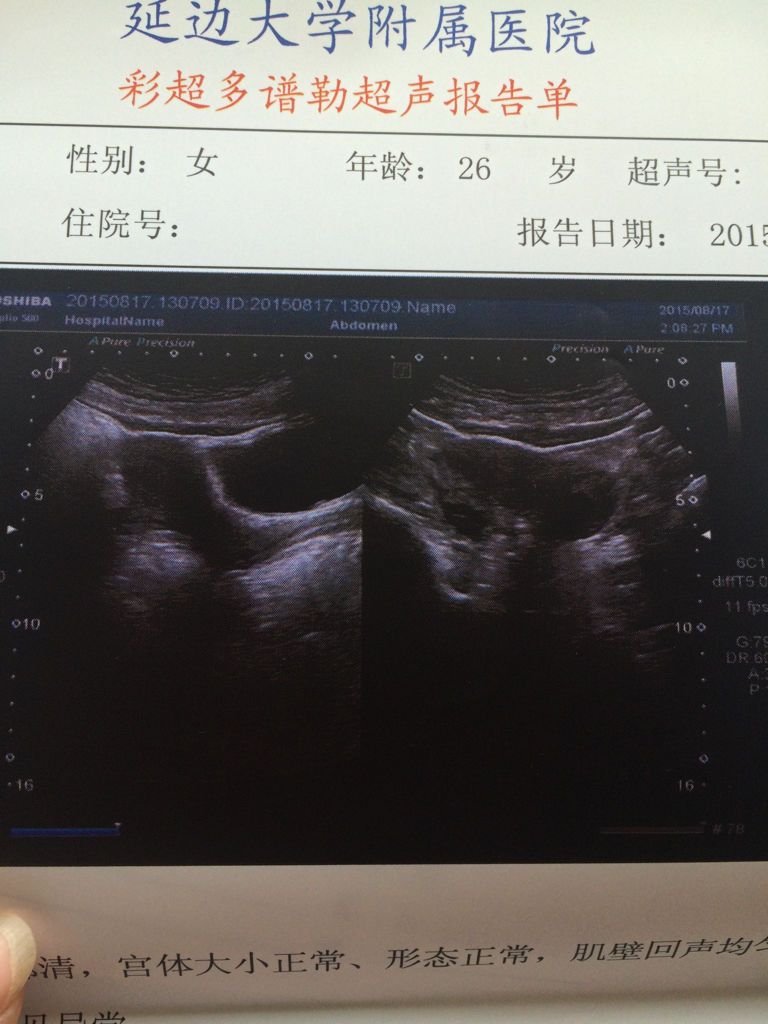

2015年8月17号做B超说有大卵泡,麻烦帮我看下面左边还是右边,今天19号,卵子大概什么时候排出 2015年8月17号做B超说有大卵泡,麻烦帮我看下面左边还是右边,今天19号,卵子大概什么时候排出,谢谢 点击展开 ァà?i-婷婷 2015-08-19 15:22 满意回答 你好,很高兴为你解答问题。图片看不过布清楚。你把你17号做的卵泡大小给我发一下!一般卵泡某乔是2.0左敢贵掏右就可以排的! 136*****535_el9I 2015-08-19 16:19 宝宝知道提示您:回答为网友贡献,仅供参考。 相关问题 月经第21天b超内膜13,右边是囊块,左边卵泡19×14这样可以怀孕吗? 卵子排出后B超会显示什么结果呢?如果不见有卵泡液只见黄体是不是表示已经排出很久了呢? 精子和卵子结合了,B超还会看到有卵泡吗?